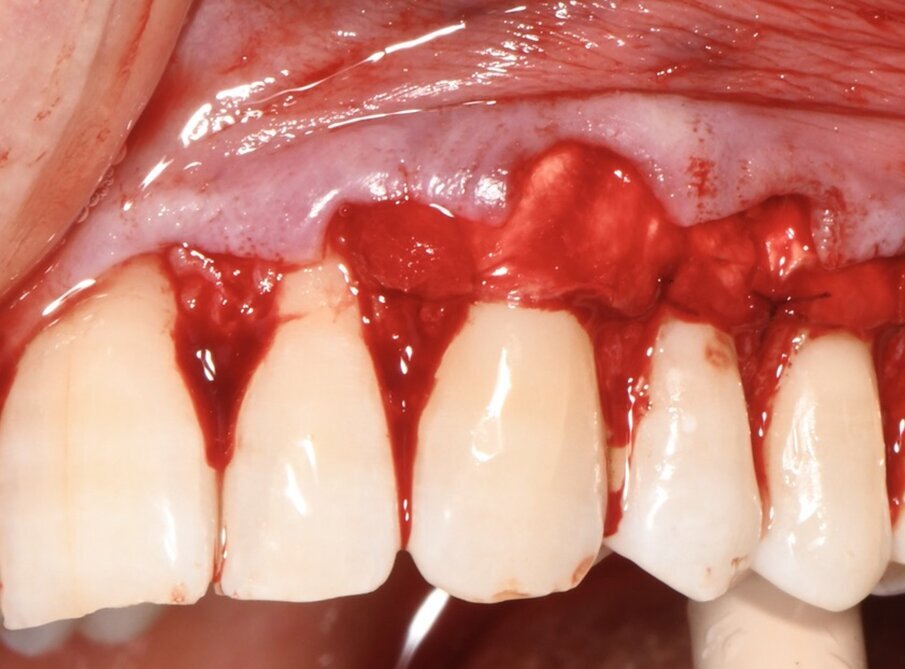

Dopo avere eseguito le incisioni primarie si provvedeva a elevare e mobilitare il lembo con tecnica mista: a spessore parziale in corrispondenza delle papille fino all’altezza del margine apicale delle recessioni, a spessore totale fino al raggiungimento della linea muco-gengivale e infine a spessore parziale apicalmente alla linea muco gengivale per la mobilizzazione in direzione apicale del lembo (Fig. 4). Il sito ricevente è stato trattato mediante levigatura radicolare meccanica della quota di radice esposta in cavo orale dalla recessione e disepitelizzazione delle papille anatomiche. Successivamente la matrice tridimensionale collagenica veniva sagomata in modo da coprire le radici esposte dal 23 al 25 e stabilizzata in sede con suture alla base delle papille anatomiche (Fig. 5). La matrice collagenica, una volta posizionata asciutta nel sito ricevente in modo da facilitarne la sutura, aderiva naturalmente ai tessuti. La matrice veniva suturata senza tensione con punti staccati, alla base delle papille anatomiche, con un filo Polyglactine 6-0 ago 3/8 Reverse - cut Surgicryl (SMI AG Steinberg 8 - 4780 ST.VITH) (Fig. 6).

Fig. 5 - Apposizione della matrice collagenica tridimensionale di origine equina, fissata con punti staccati alla base delle papille anatomiche, imbibita di sangue per ottenere la copertura radicolare degli elementi 23-25.

Fig. 6 - Il lembo a busta è posizionato coronalmente e fissato in sede con punti sospesi.